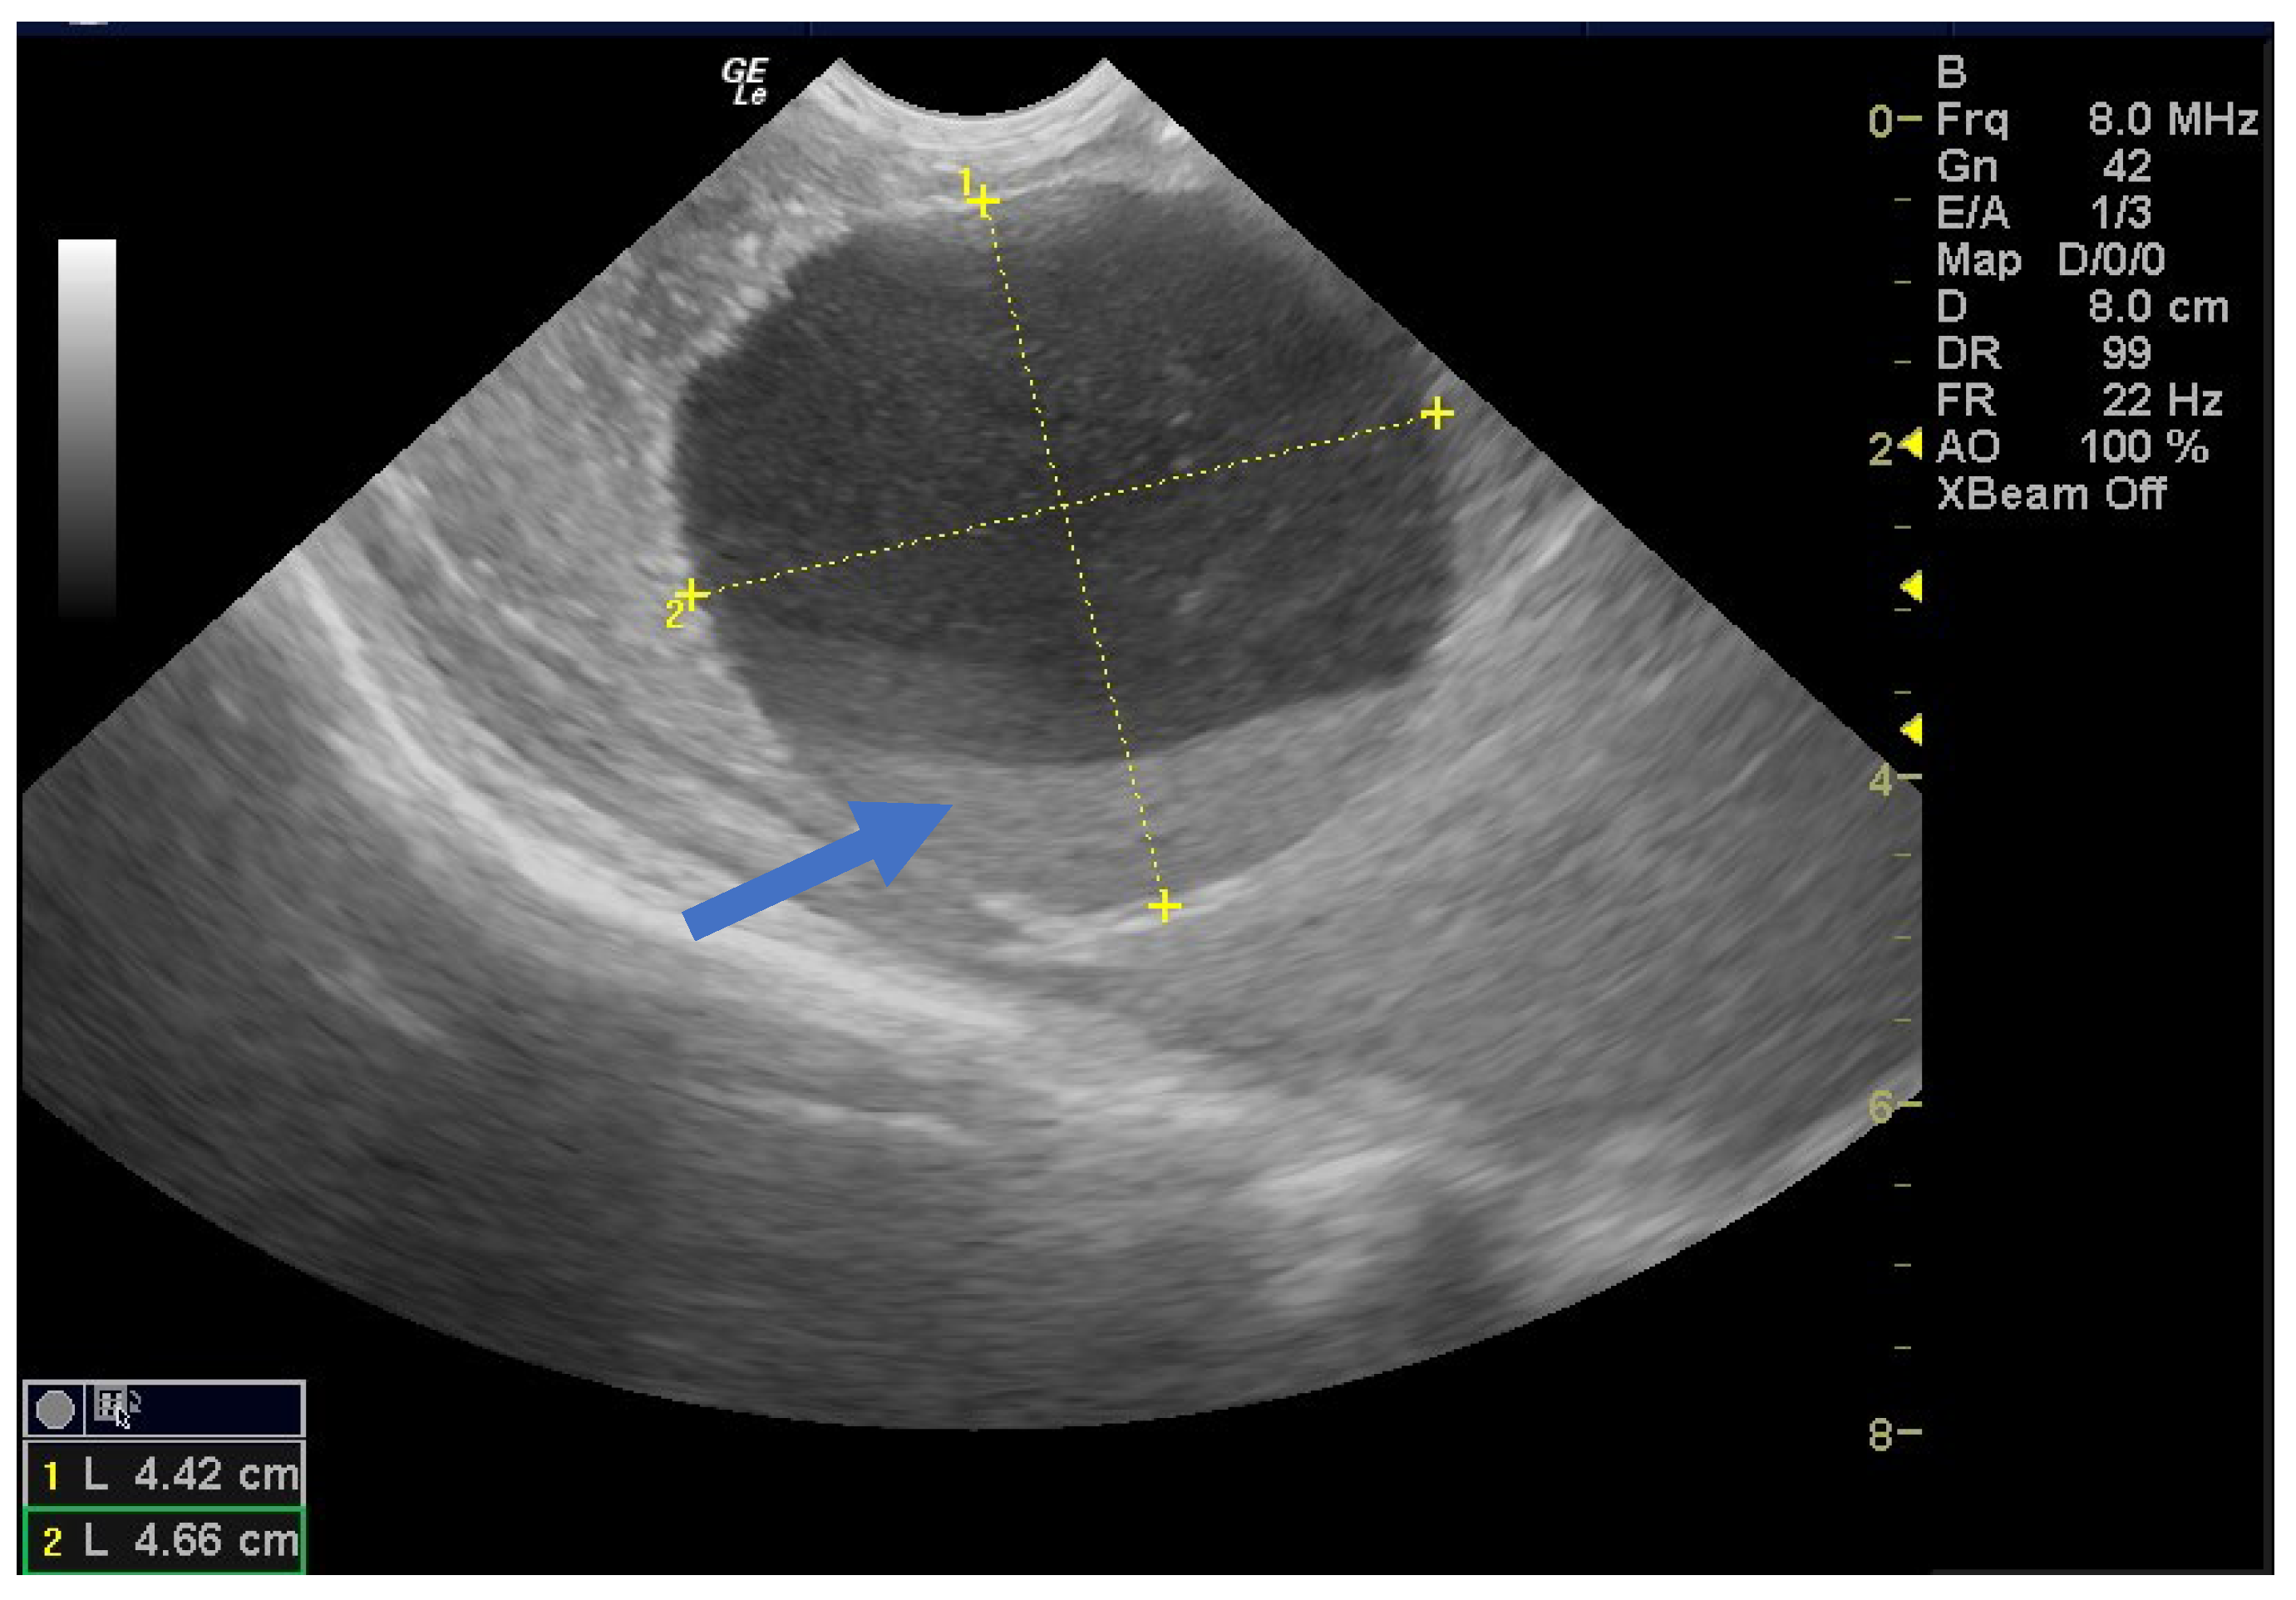

Of the nine simple cysts, seven regressed spontaneously within the first two months after birth (Figure 5 and Figure 6).

Figure 5.

Ultrasound image of a simple cyst with an intracystic blood clot (arrow) at the age of 2 weeks postpartum, which regressed spontaneously at 2 months.